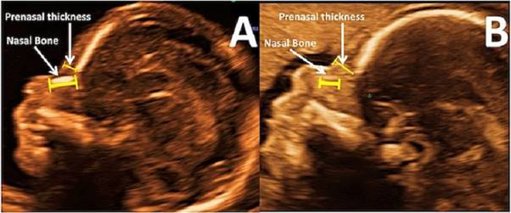

Bên cạnh các chỉ số về chiều dài đầu, mông, tim thai,... thì chiều dài xương mũi cũng là một yếu tố phản ánh sự phát triển bình thường của thai nhi. Vậy thời điểm nào có thể đo được chính xác chiều dài xương mũi thai nhi và chỉ số này phản ánh điều gì, nội dung bài viết dưới đây sẽ cùng bạn tìm h...